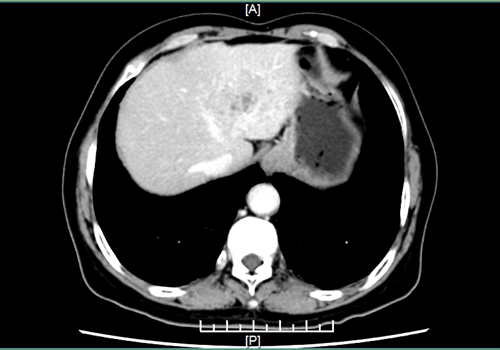

大约3个多小时后,这台“腹腔镜下左半肝切除术+胆囊切除术+中肝静脉部分切除重建”手术顺利完成。术中出血量少,患者病情平稳。

术后影像图。院方供图